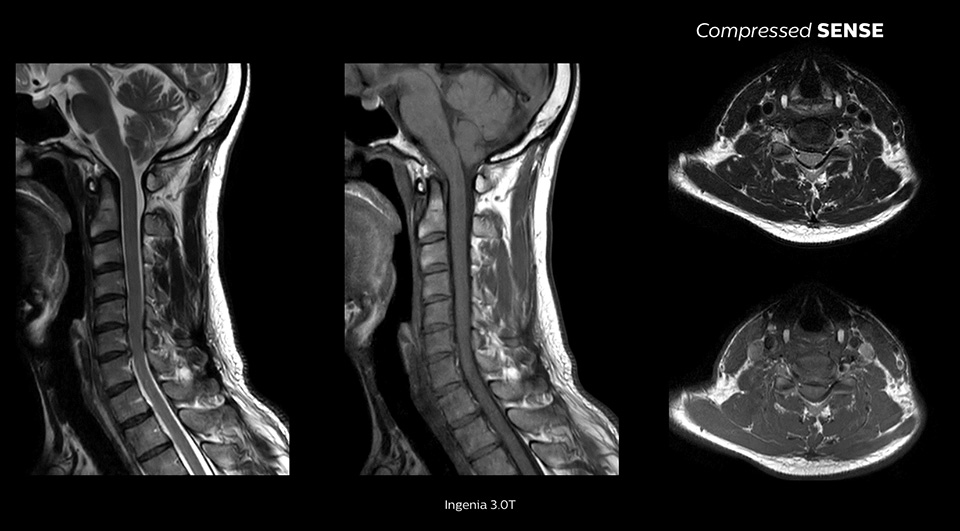

We are essentially running our standard protocols and just turning Compressed SENSE on and seeing a 20% reduction in scan time. None of the physicians know if it’s a Compressed SENSE scan versus a non-Compressed SENSE scan when they’re reading."

John P. Karis, M.D. Director of MRI and brain imaging, Department of Neuroradiology at Barrow Neurological Institute, USA

Can be used for all anatomical contrasts, in both 2D and 3D

Enables up to 64% improvement in spatial resolution1